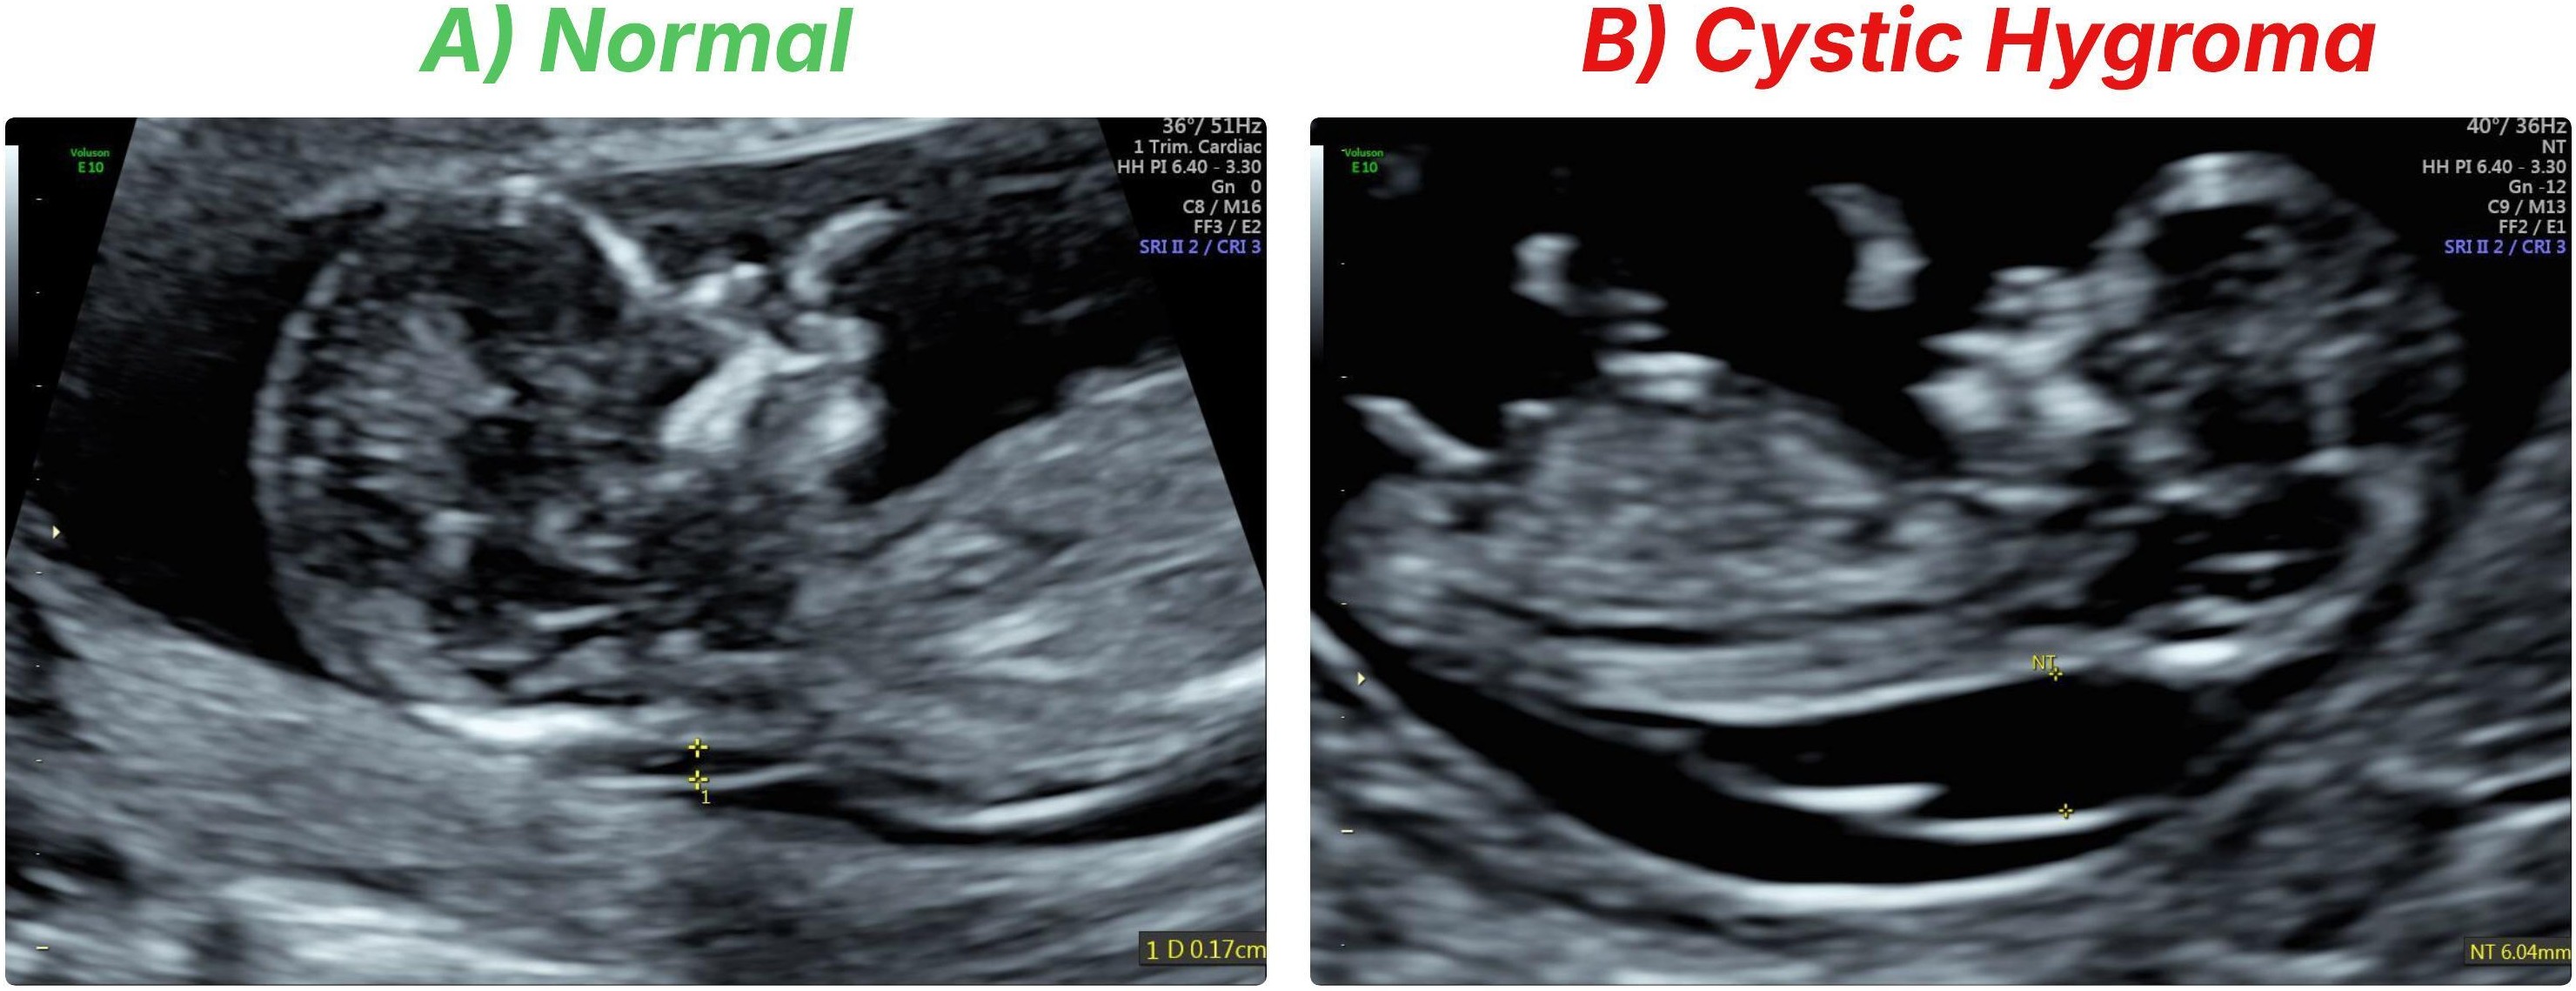

Refer to caption

Figure 1: Comparison of first-trimester fetal ultrasound images. A) Normal fetus with typical NT thickness. B) Fetus with cystic hygroma, showing a markedly enlarged, multiloculated nuchal fluid collection consistent with lymphatic malformation.

One important prenatal finding on obstetric sonography is cystic hygroma. Cystic hygroma is a lymphatic lesion, appearing as a fluid-filled, multiseptated cystic mass, that is often seen on the fetal neck region, also known as the nuchal area. It is an important sonographic finding due to its strong correlation to severe fetal pathology. Cystic hygroma in the first trimester is highly predictive for aneuploidies (or abnormal number of chromosomes). In fact, over 50% of fetuses with first-trimester cystic hygroma will have aneuploidy, including Down syndrome (trisomy 21), Turner syndrome (45, X), or trisomy 18 [8]. Cystic hygroma also has a high co-occurrence with other structural malformations (e.g., cardiac defects) and is highly predictive for fetal demise [8]. In fact, cystic hygroma is one of the highest prenatal risks for genetic syndromes and poor outcomes when compared to a simple increased Nuchal Translucency (NT) [8]. As a result, early identification of cystic hygroma on ultrasound can play an important role in prenatal prognostication and perinatal management. In practice, cystic hygroma is usually visualized as an enlarged NT (Fig 1B) with septations on the 11-14 week scan, and is often thicker than the normal cut-off for gestational age [7]. The prevalence of cystic hygroma has been reported to be around 1 in 285 pregnancies in a general obstetric population [7], so it is an uncommon, but important, sonographic finding to be able to identify. This prenatal finding often results in invasive testing, genetic counselling, and may even impact management of the pregnancy, highlighting the importance of accurately and consistently detecting cystic hygroma.

Recently, there have been efforts to apply supervised DL to automate cystic hygroma diagnosis from ultrasound images. Walker et al. [9] developed a convolutional neural network (CNN) based on the DenseNet-169 architecture to distinguish first-trimester mid-sagittal scans as either normal or showing a cystic hygroma (an example of each class is shown in Fig 1) [9]. Their model was trained on a curated dataset of 289 ultrasound images (129 cystic hygroma cases, 160 normal controls) and achieved 93% classification accuracy (sensitivity 92%, specificity 94%) in distinguishing cystic hygromas from normal fetuses [9]. This proof-of-concept study demonstrated that DL can attain expert-level performance in early anomaly detection. Moreover, Gradient-CAM [18] visualizations confirmed that the model’s decisions were driven by the fetal neck region, aligning with clinical expectations [9]. While encouraging, the DenseNet-based approach has notable limitations. One of them is that the DenseNet-169 model had to be trained from scratch on ultrasound images because conventional transfer learning from natural image data (ImageNet) [19] was deemed suboptimal due to the domain mismatch [9]. Ultrasound images have fundamentally different textures and content compared to everyday photographs, so an ImageNet-pretrained CNN may not provide useful features [9]. Training a deep CNN without any pretrained initialization on only a few hundred images is far from ideal – it risks converging to local minima or learning spurious features. In Walker et al.’s study [9], extensive data augmentation and cross-validation were employed to mitigate this risk [9], but the situation underscores a general challenge: supervised DL in medical imaging is often bottlenecked by scarce labelled data and poor transferability of models pretrained on non-medical images [1]. These limitations motivate the exploration of approaches that can leverage the abundance of unlabeled medical images to learn robust representations, reducing the dependency on large labelled datasets.